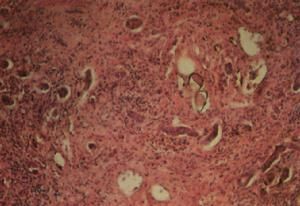

腦血吸蟲病病理說明

感染使腦膜局限性或廣泛性形成不規則的肉芽腫,淋巴細胞,漿細胞或多核巨細胞浸潤。腦呈不同程度的水腫,黴菌沿血管周圍和軟腦膜下聚集,形成多數小囊樣病灶,呈急性或慢性化膿性炎症反應,甚至形成腦膿腫或肉芽腫,多位於腦實質內,偶見腦室內。在膿腫和肉芽腫中可見大量黴菌體或菌絲。不同種類的黴菌感染,引起的病理變化也不相同,白色念珠球菌常引起小灶性化膿和肉芽腫;隱球菌早期形成膠凍樣病變,無纖維包膜,晚期則形成肉芽腫;放線菌主要形成多發性膿腫和肉芽腫,膿腫壁呈黃色,膿液含"硫磺顆粒"。慢性病程者常有廣泛腦萎縮。症狀